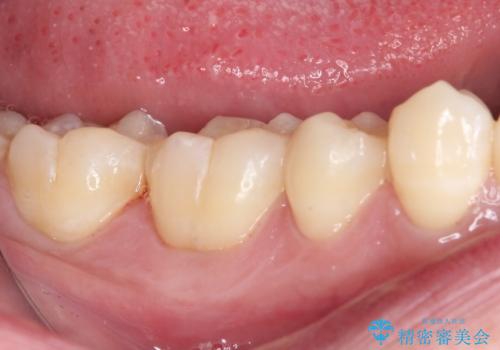

- 右下の奥歯が噛んだ時に痛み、冷たいものがしみることを主訴として来院された患者様です。

精査の結果、歯が欠けていてその下に虫歯が認められました。

また、咬合面(歯の噛む面)に以前治療した樹脂の詰め物があるため、一度外して虫歯を完全に除去し、

精度の高いセラミックインレーにて修復処置することとしました。

噛んだ時の痛みや、冷たいものがしみる症状はなくなり、見た目も自然でどこが詰め物かわからないと、患者様は大変満足されました。